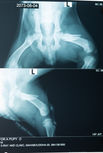

雖然尼泊爾人普遍對社區狗友善,但當狗隻生病或受傷時,因著欠缺知識和資源,他們往往未能加以救助,因此,社區狗並不會像我們家中的寵物犬那麼幸運,往往不會獲得治療。這也再一次說明為何推行TNR是治本的手法。今年,在兩星期的絕育計劃期間,我們共處理了4個狗女的性病腫瘤 (TVT), 2個子宮蓄膿(Pyometra)以及一1個幼犬大腿骨折的個案。我們慶幸及時找到牠們並作出適當治療,這可說是我們在進行 TNR 計劃的同時的小小 ‘bonus’.

2) Saved our furry friends’ lives in time